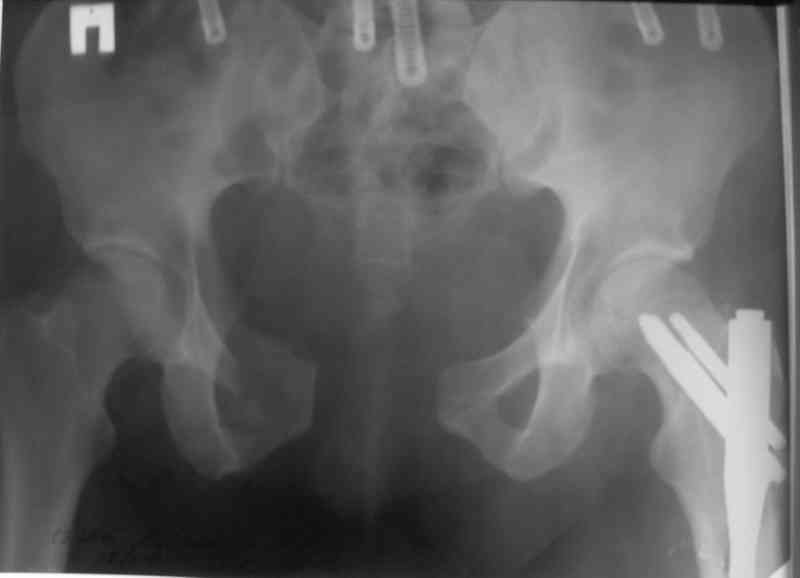

Вчера прооперировал больного.

Попытка низвести половину таза на тракционном столе ( скелетное вытяжение за бедро) безуспешная.

из переднего доступа добрался до правого КП сочленения , все запаяно костью, с помощью 2 шанцев винтов в крестец и подвздошную кость и элеватора репозиция, контроль ЭОП

и двумя пластинами фиксация.

Спереди, аппарат как рекомендовал Джолдас.

Снимки плохого качества( очень темные) завтра переделают и пришлю на конференцию.

На мой взгляд, смещение устранено и фиксация выглядит вполне анатомичной.

В приложении послеоперационные картинки.

Всего доброго,

Спасибо всем принявшим участие в обсуждении,

Чекашкин Е.И.